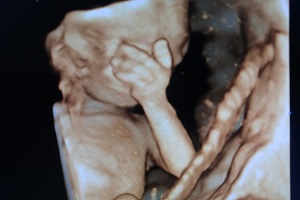

4D ANOMALY SCAN

5D SONOGRAPHY